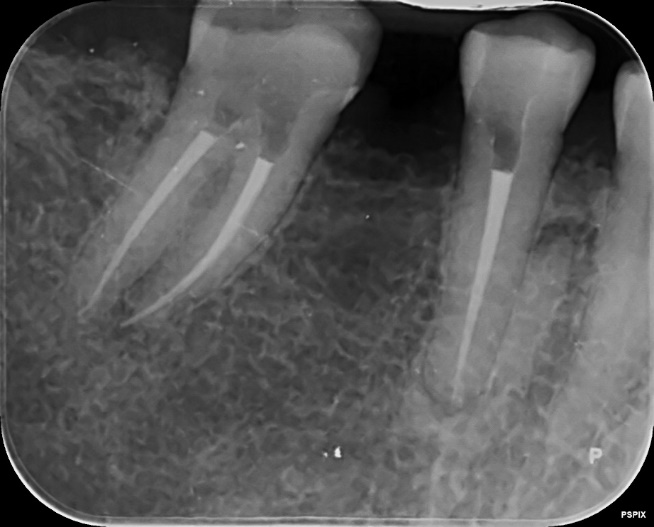

Lower Molar and premolar Primary root canal treatment